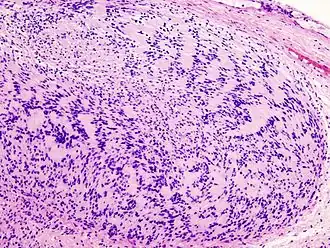

| Микропрепарат опухоли окраска гематоксилин-эозин. | |

Невринома состоит из веретенообразных клеток с палочкоподобными ядрами. Клетки и волокна опухоли образуют «палисадные» структуры (ядерные палисады, тельца Верокаи) с участками, состоящими из волокон[2].

Традиционно различают два гистологических типа неврином: тип Верокаи, или тип А, и тип Антони, или тип Б. Данное разделение условно и практического значения для диагностики не имеет. Советский нейрохирург, академик АМН СССР Б. Г. Егоров при исследовании неврином слухового нерва обнаружил, что их структурное многообразие зависит не от свойств опухолевой ткани, а от деструктивных и рубцовых процессов[1].

Микроскопическое строение опухоли на разных стадиях роста может быть различным в зависимости от интенсивности дистрофических процессов и нарушений кровообращения. Нарушения кровообращения сопровождаются скоплением гемосидерина и разрастанием фиброзной ткани. Всё это создаёт пёструю гистологическую картину[1].